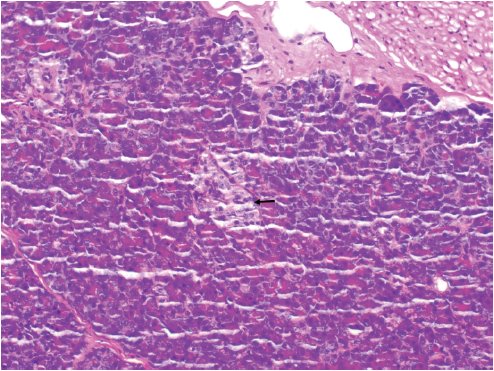

病理提示,胃固有肌层内可见腺体分叶状分布,无异型,考虑为胰腺组织,以胰腺腺泡为主,可见胰岛细胞(图5和图6)。

图5 病理(×40):胃固有肌层内可见腺体分叶状分布,无异型,考虑为胰腺组织,以胰腺腺泡为主

图6 病理(×200):胰腺组织中可见胰岛细胞(黑色箭头)